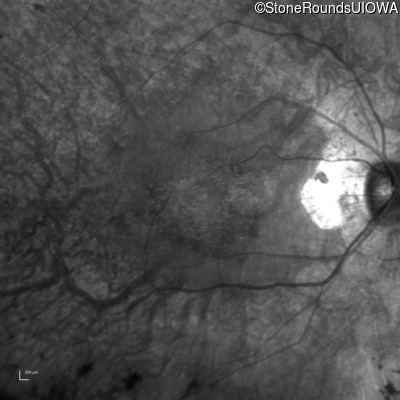

Infrared Fundus Photograph - Right - 20/25 -2 sc

Exemplar

Infrared Fundus Photograph - Left - 20/25 sc